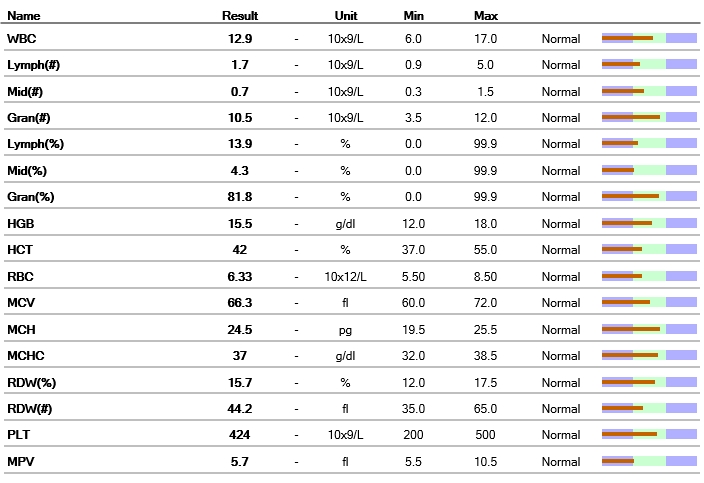

빈혈, 염증 수치 등을 평가하는 혈구 검사 결과입니다